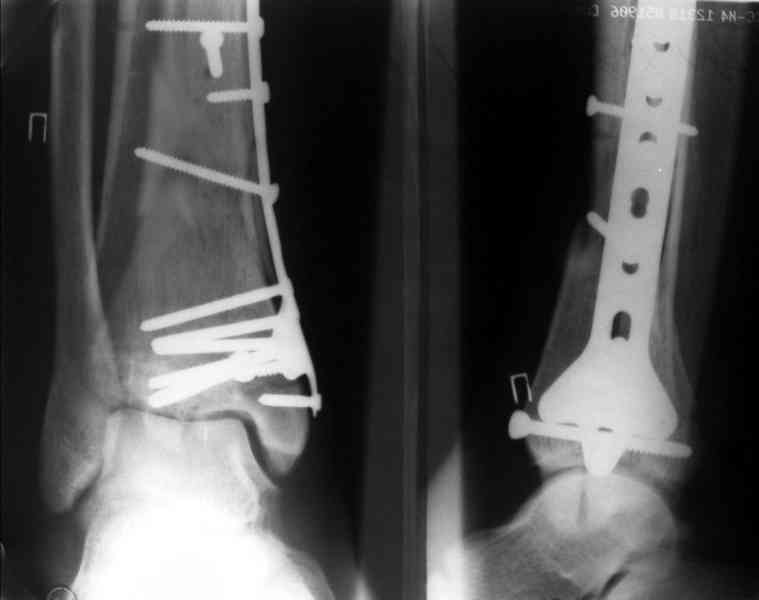

Посылаю результат лечения предыдущего больного через год.

С уважением Дрягин